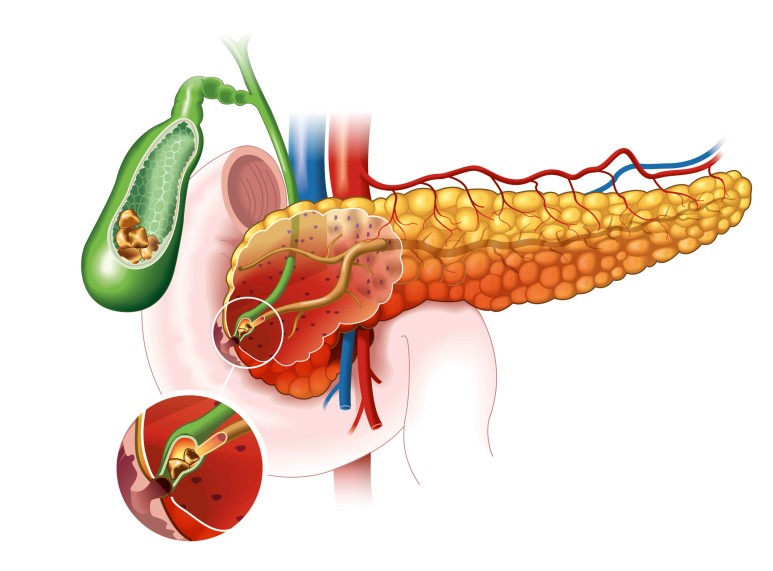

담관 담석과 양성 협착의 경우 보다 종양으로 인하여 담관이 막힐 경우 담관 확장이 더욱 심해집니다.

또한 담낭 관원위부의 총 담관이 막히는 경우 담즙의 압력 상승으로 담낭까지 확장될 수 있습니다.

그 원인이 총 담관 담석의 경우 담낭 확장이 이루어지지 않는 경우가 많은데 이는 완전 폐쇄가 아닌 부분 폐쇄로 담즙이 부분적으로 흘러나와 담낭 내의 압력을 높이지 않기 때문입니다.

또한 총 담관 담석의 유래가 담낭인 경우에는 담낭에 만성적인 염증이 동반되어 섬유화가 진행되어 담낭의 확장이 불가능하기 때문입니다.

따라서 신체검진시 손으로 만질수록 담낭의 크기가 커지고 있으나 압통이 없는 경우에는

이를 Courvoisier 징후라고 하는데, 담관폐쇄의 원인이 총담관석에 의한 것이 아니라 악성폐쇄일 가능성이 높습니다.

담관폐쇄로 인해 담즙이 정체되어 있는 경우 세균증식이 자주 이루어지며 담관염이 발생합니다.담석으로 막혔을 때 흔히 발생하며 담석에 세균이 많이 분포되어 있어 부분적으로 폐쇄되는 경우 사이를 통해 세균이 담관 상부로 유입될 수 있기 때문입니다.

악성에 의한 담관 폐쇄에는 담관염의 발생이 드물지만 폐쇄가 장시간 계속되면 발생할 가능성이 있습니다.